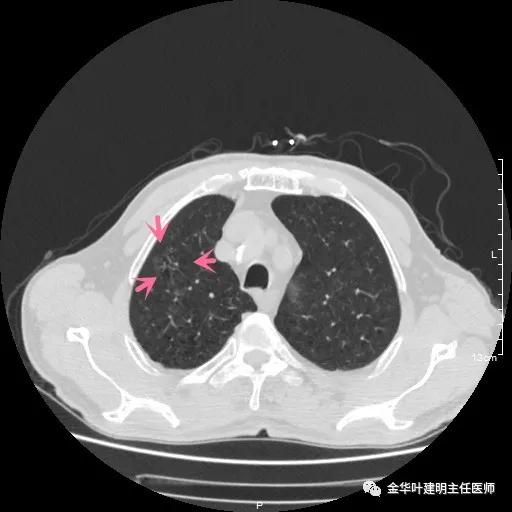

以上示左上叶病灶2。病灶虽然似慢性炎,但有收缩力,有毛刺征,在右侧诸多病灶考虑多原发肺癌的前提下,此灶是恶性的可能性非常大,不能单纯认为其是慢性炎性病灶。就此单灶来看,可以局部切除病检,若示浸润性腺癌,则有肺叶切除的指征。